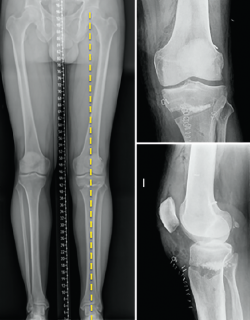

We should bear in mind that although the indication of osteotomy resides in varus correction (coronal plane), the osteotomy will also affect the sagittal and axial planes (Figure 5).

Figure 5. Control computed axial tomography view of an opening valgus-producing tibial osteotomy.